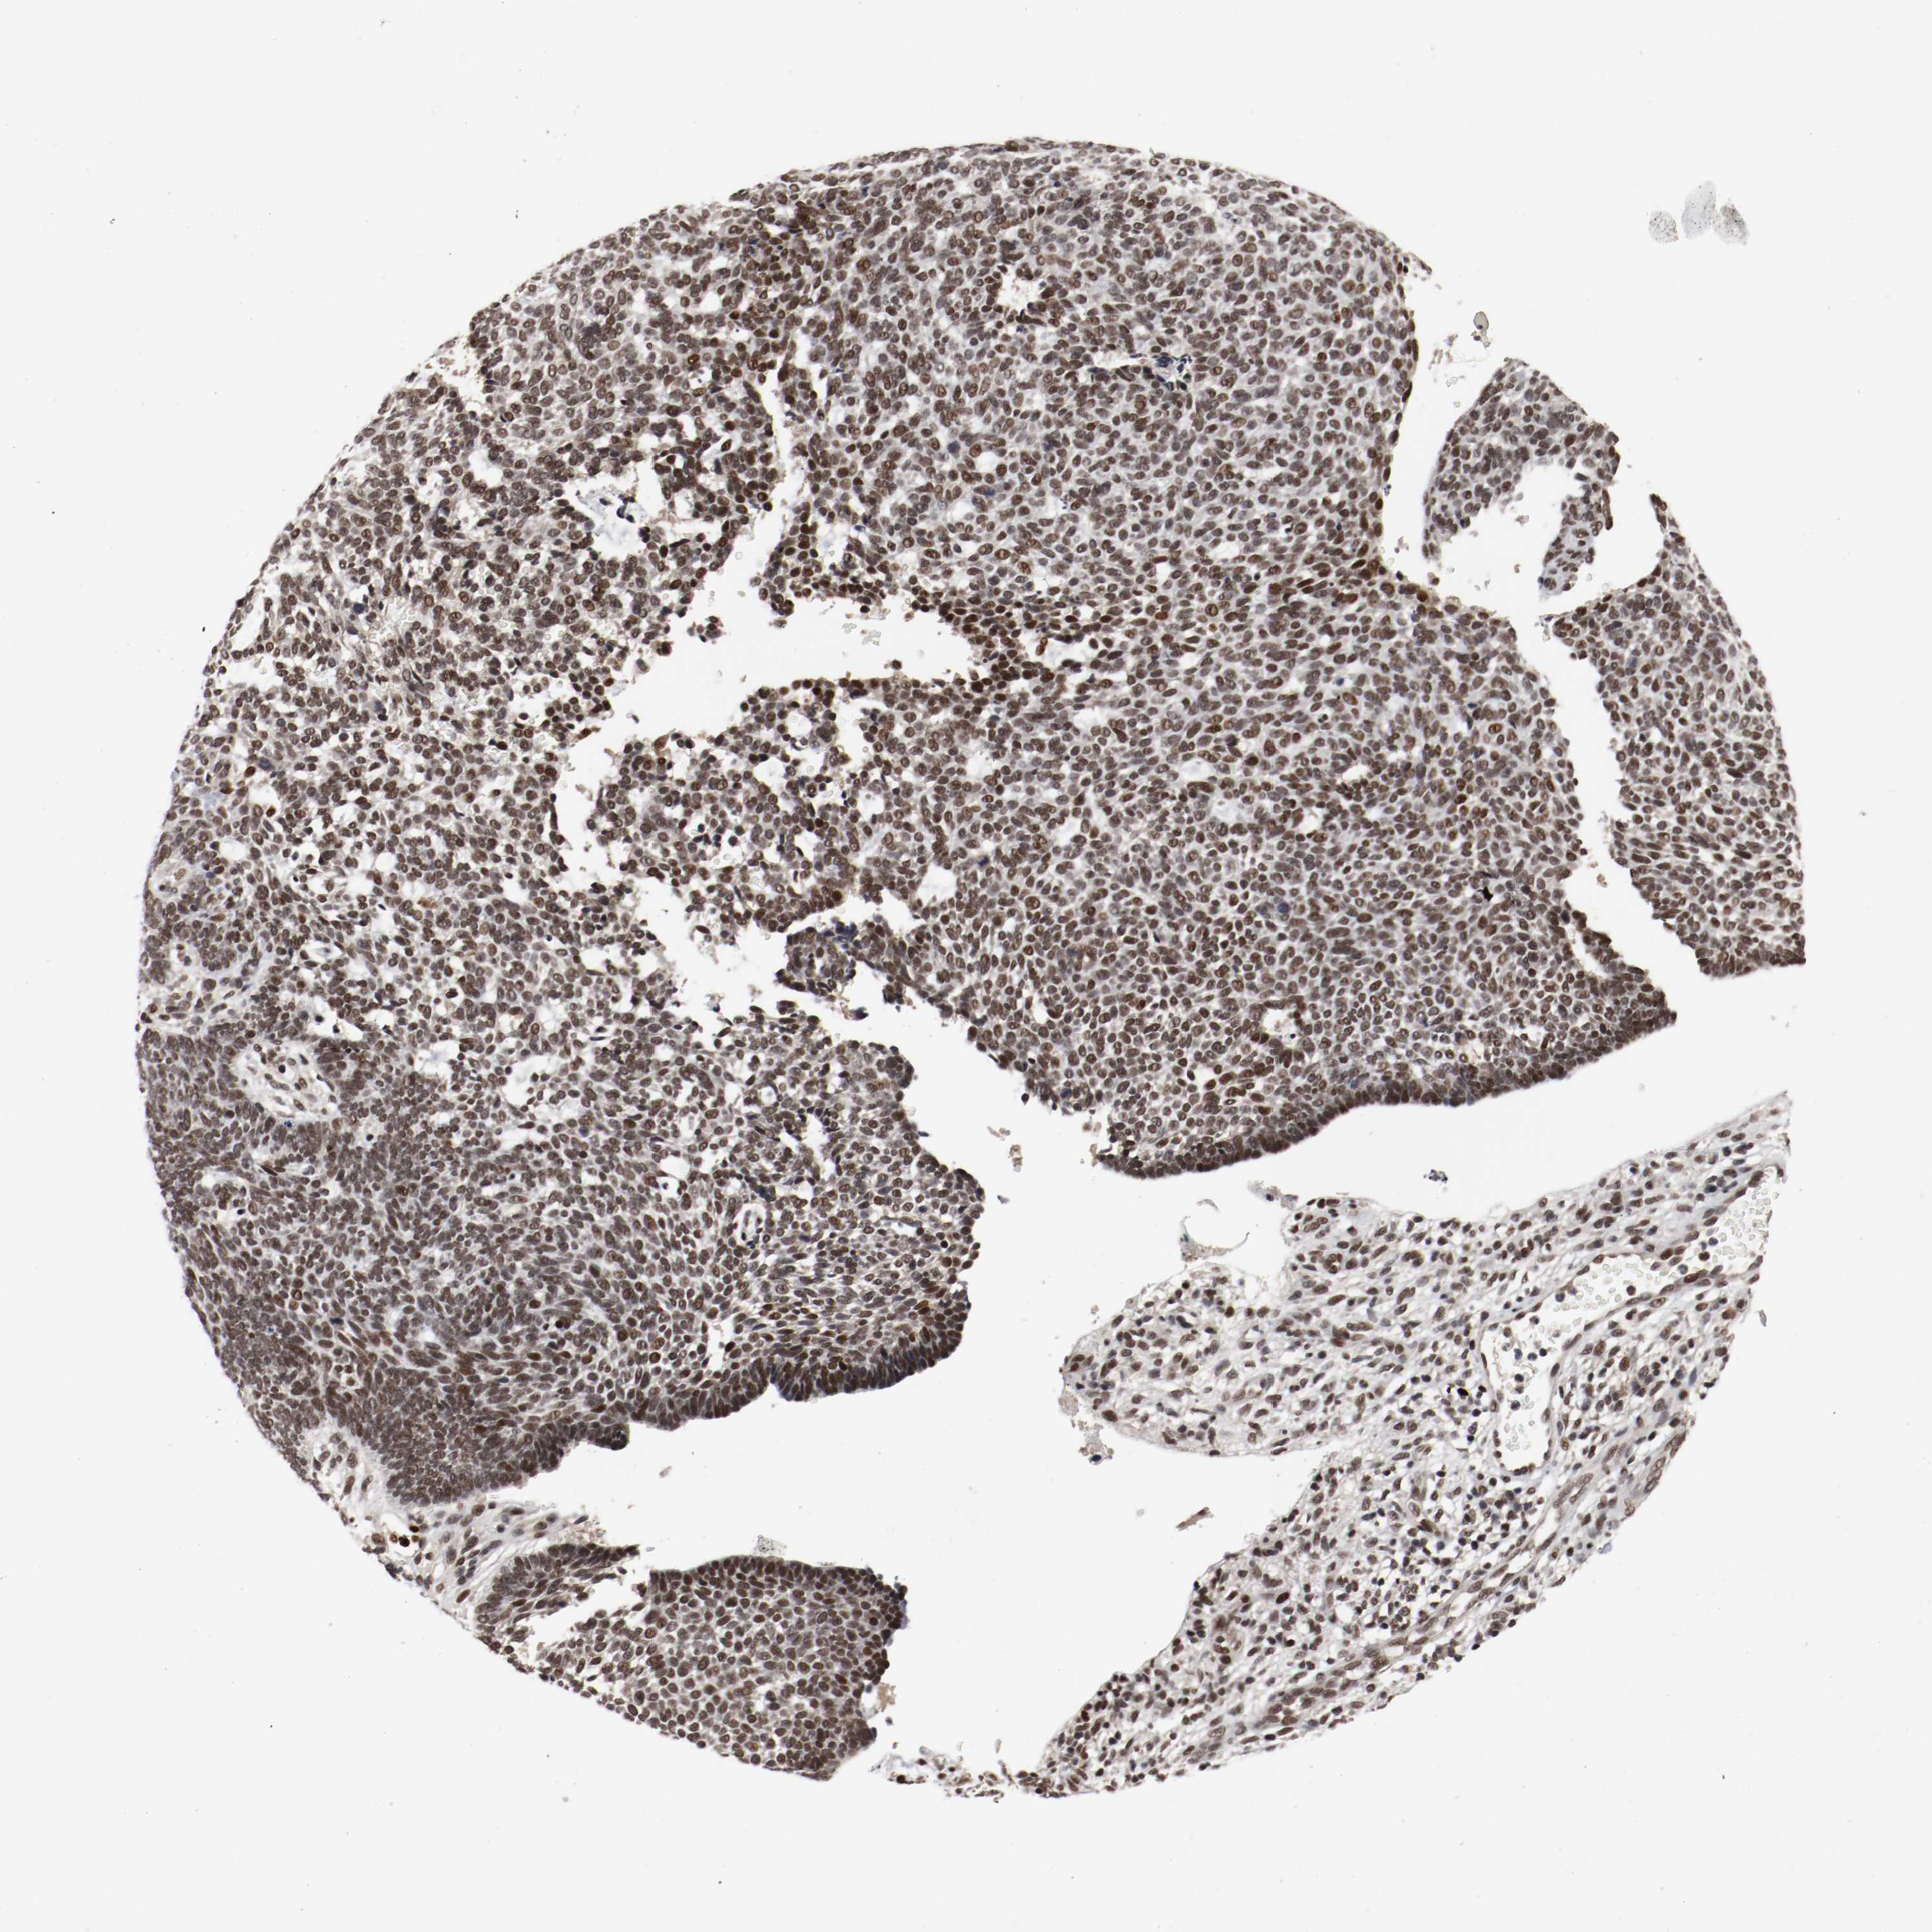

SKIN CANCER - Protein expressioni

A mouse-over function shows sample information and annotation data. Click on an image to view it in a full screen mode. Samples can be filtered based on level of antibody staining by selecting one or several of the following categories: high, medium, low and not detected. The assay and annotation is described here.

Each image is clickable and will lead to virtual microscopy that enables deeper exploration of all samples and also displays staining intensity scores, fraction scores and subcellular localization as well as patient and tissue information for each sample.

Antibody HPA004794

Staining

High

Intensity

Strong

Quantity

>75%

Location

Nuclear

Squamous cell carcinoma, NOS

Basal cell carcinoma